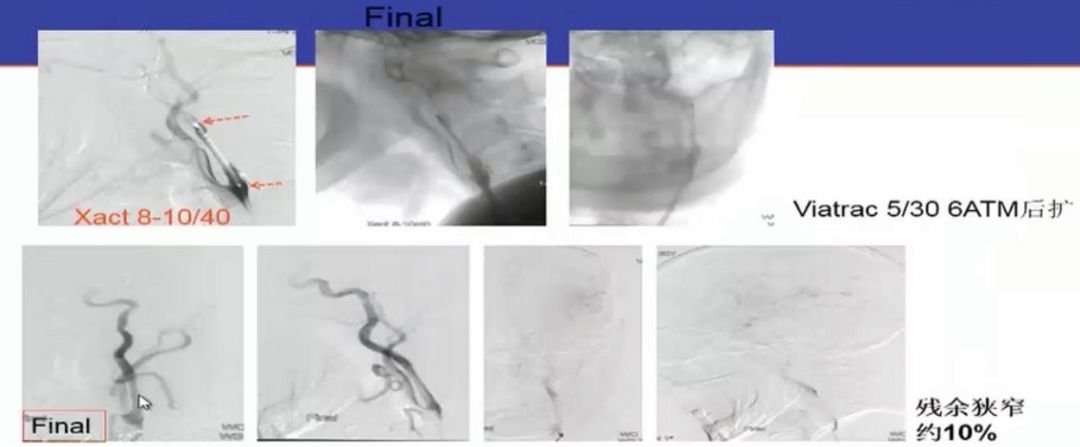

图2 ADAPT技术应用于串联病变